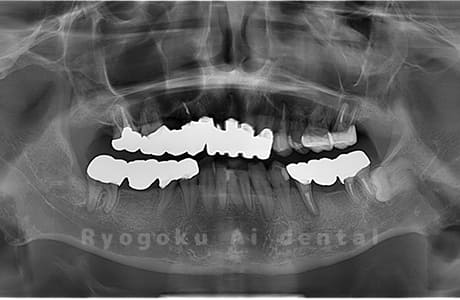

Case02

- 原因

- 下顎の水平埋伏智歯

- 治療内容

- 下顎の水平埋伏智歯を抜歯

<リスク・副作用>

手術後は痛み、腫れ、痺れなどの副作用が生じる場合があります。